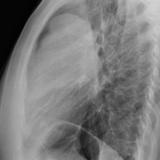

Case 9 Thymoma Lat

Date: 04/04/2010

Views: 3260